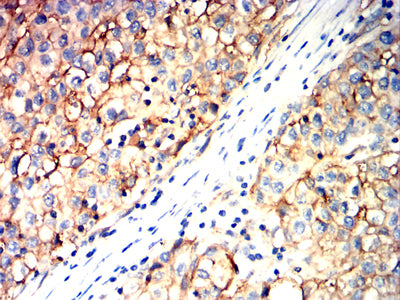

| IHC | IHC:1/100-1/200;IHF:1/50-1/200 | Human,Mouse,Rat |